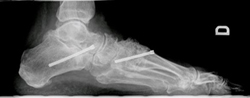

Hay muchos tipos de cirugía para tratar las deformidades estructurales. Los principales son:

- Transferencia tendinosas

- Secciones tendinosas

- Osteotomías (correcciones óseas)

- Artrorisis (prótesis limitadoras de la movilidad)

- Artrodesis (fijación de articulaciones).